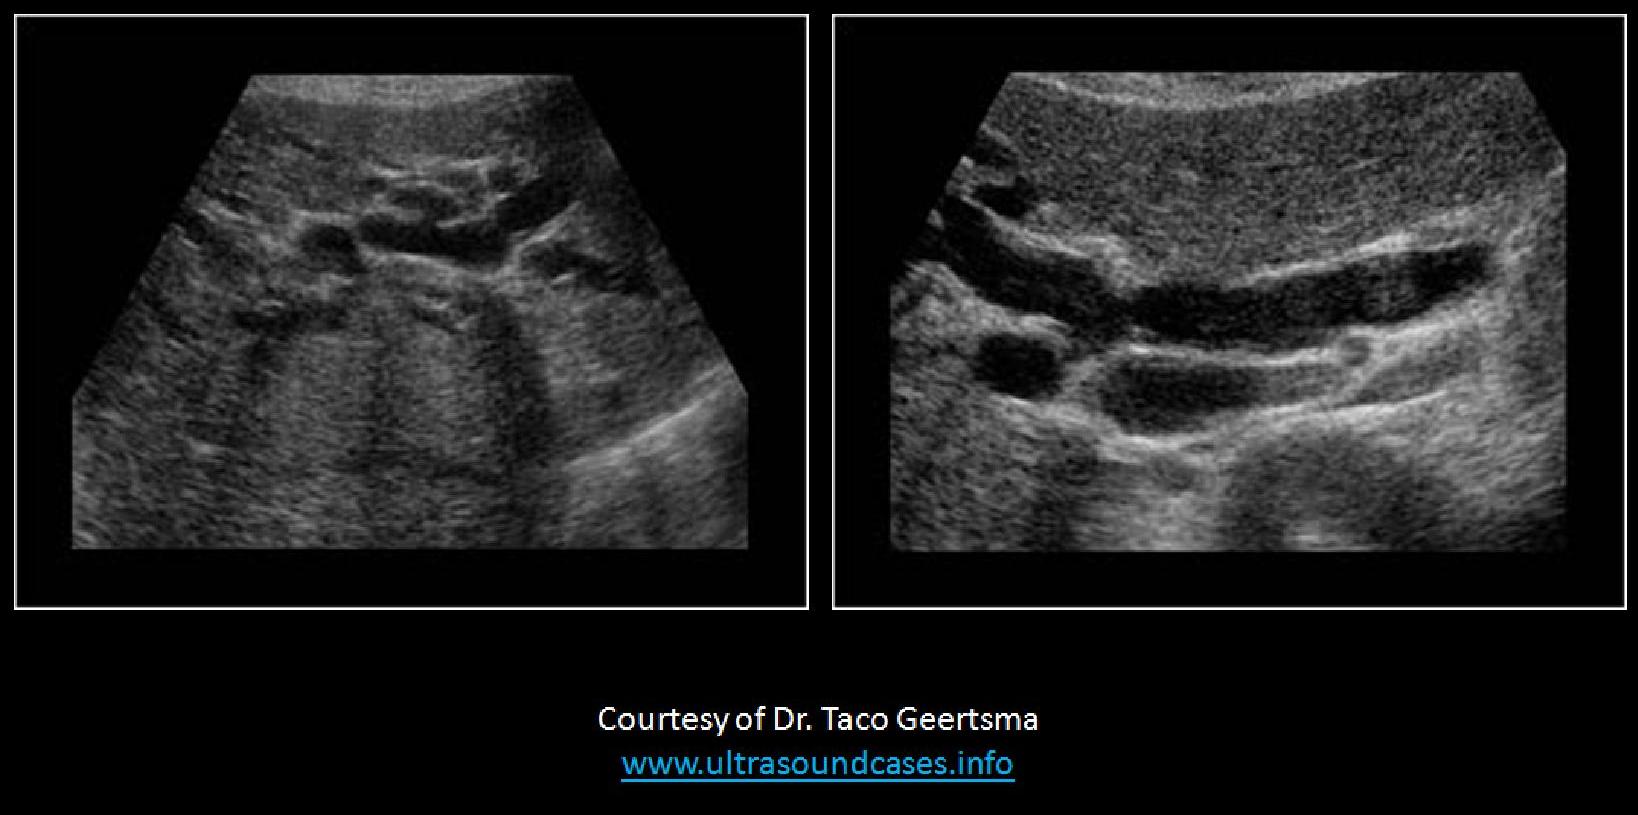

a 55 year-old male presents with a history of Budd-Chiari syndrome. What vessels should be evaluated with Doppler on this exam?

Hepatic veins